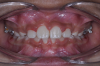

The following case illustrates the complete surgical/orthodontic treatment sequence for an impacted maxillary right central incisor. An 8½-year-old patient presented with a chief complaint of crowded teeth. The maxillary left central incisor was the only erupted incisor at the time of consultation (Figure 2 and Figure 3). Crowding was clinically diagnosed visually by the prominence of the unerupted right central incisor in the vestibule, and this was confirmed with a panoramic radiograph (Figure 4).

Fig 2. Initial situation of case involving an impacted maxillary right central incisor, frontal view (Fig 2) and occlusal view (Fig 3).

Fig 3. Initial situation of case involving an impacted maxillary right central incisor, frontal view (Fig 2) and occlusal view (Fig 3).